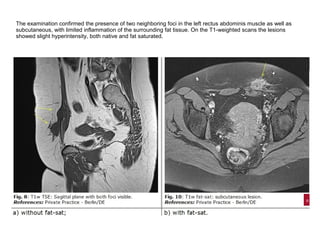

The examination confirmed the presence of two neighboring foci in the left rectus abdominis muscle as well as

subcutaneous, with limited inflammation of the surrounding fat tissue. On the T1-weighted scans the lesions

showed slight hyperintensity, both native and fat saturated.